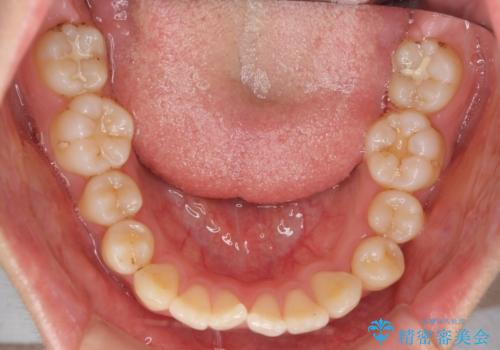

- 前歯のがたつきを気にして来院。

左下の小臼歯が捻転し、反対咬合になっていました。

先にワイヤーで部分矯正を行ってから、インビザラインの部分矯正を行いました。

専門的な話になりますが、下顎の小臼歯は円柱状の形をしており、インビザライン単独では捻転はほぼ治りません。

今回は左下の小臼歯が捻転が強く、そこが反対咬合になっていたため事前に部分矯正を行いました。